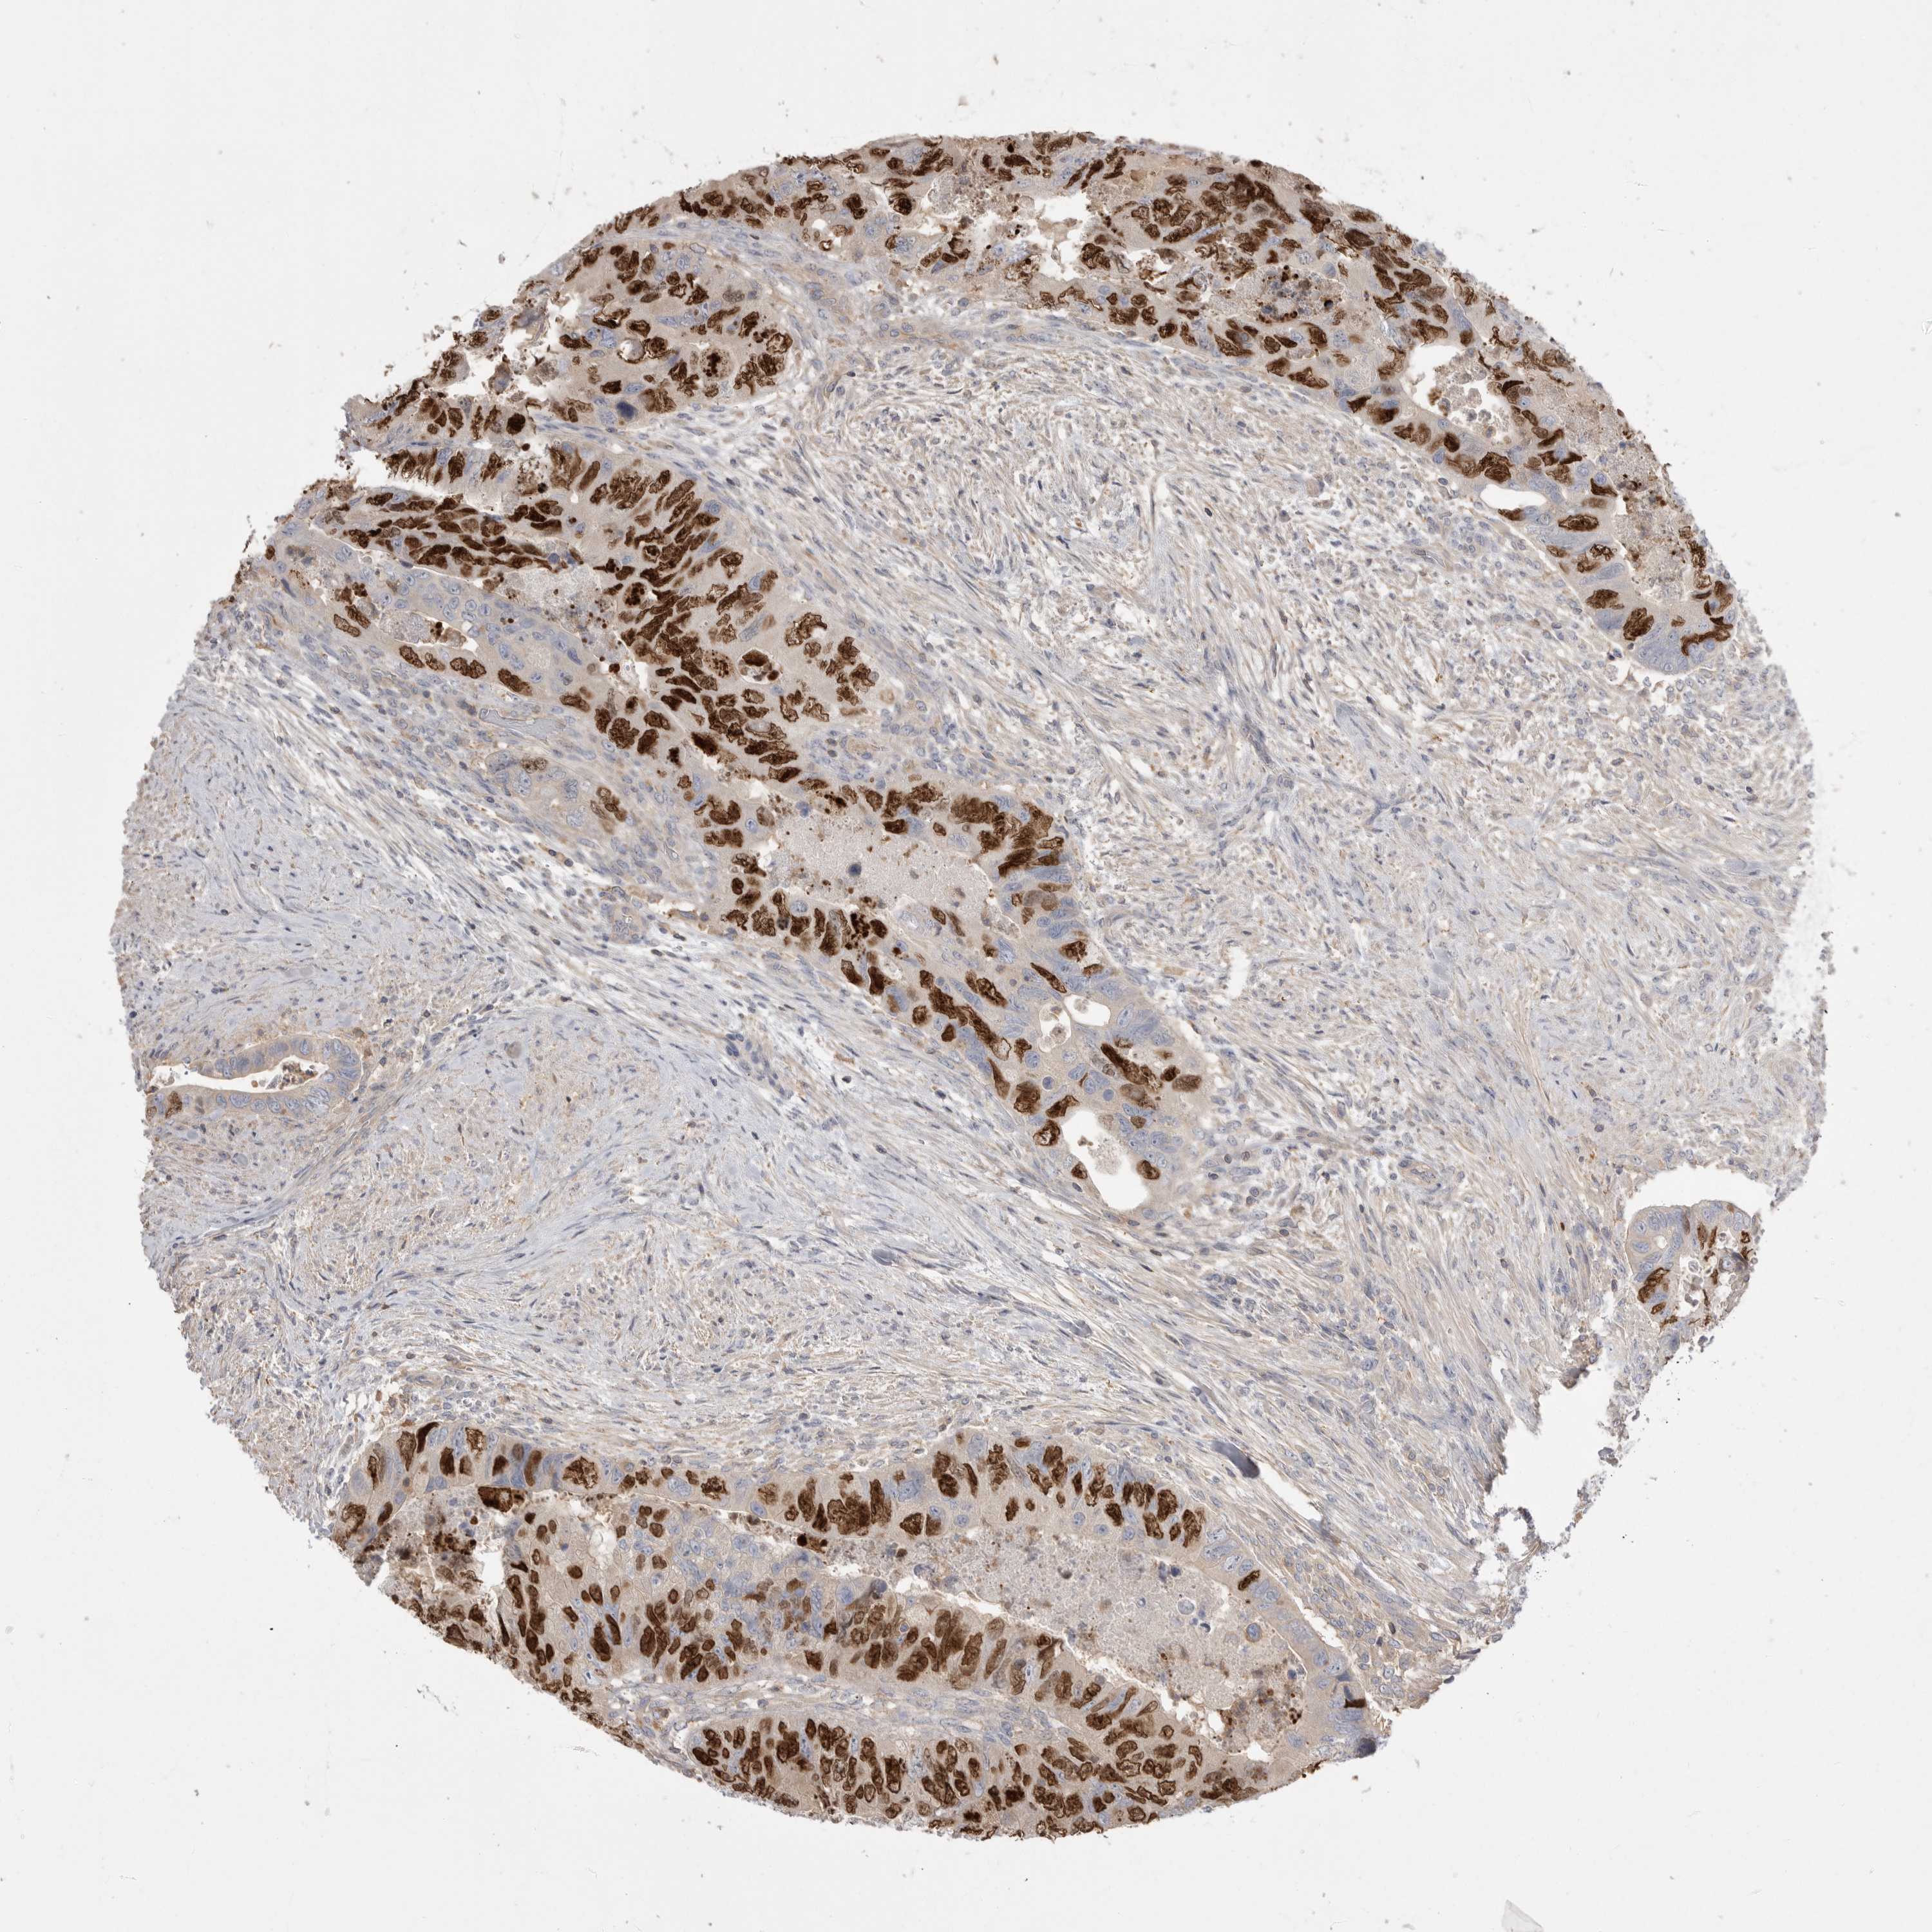

CANCER COLORECTAL CANCER Show tissue menu

Colorectal cancer

Human cancer

Colon adenocarcinoma

Rectum adenocarcinoma